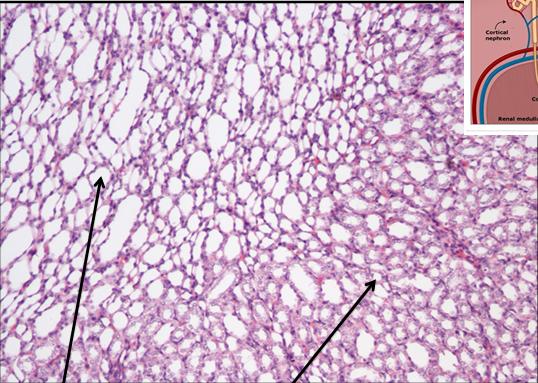

NERKA - kora nr 430

światło kanalika proksymalnego i kłębuszek nerwowy (ciałko Malpigiego)

kanaliki pośrednie - nabłonek jednowarstwowy płaski

cewki zbiorcze - nabłonek jednowarstwowy sześcienny

rdzeń nerki - trochę jak tłuszczowa ale mniejsze kropki i bardziej fioletowe, nr 430

nabłonek jednowarstwowy płaski na zewnętrznej stronie blaszki torebki Bowmana

ścianki kanalika proksymalnego to nabłonek jednowarstwowy sześcienny